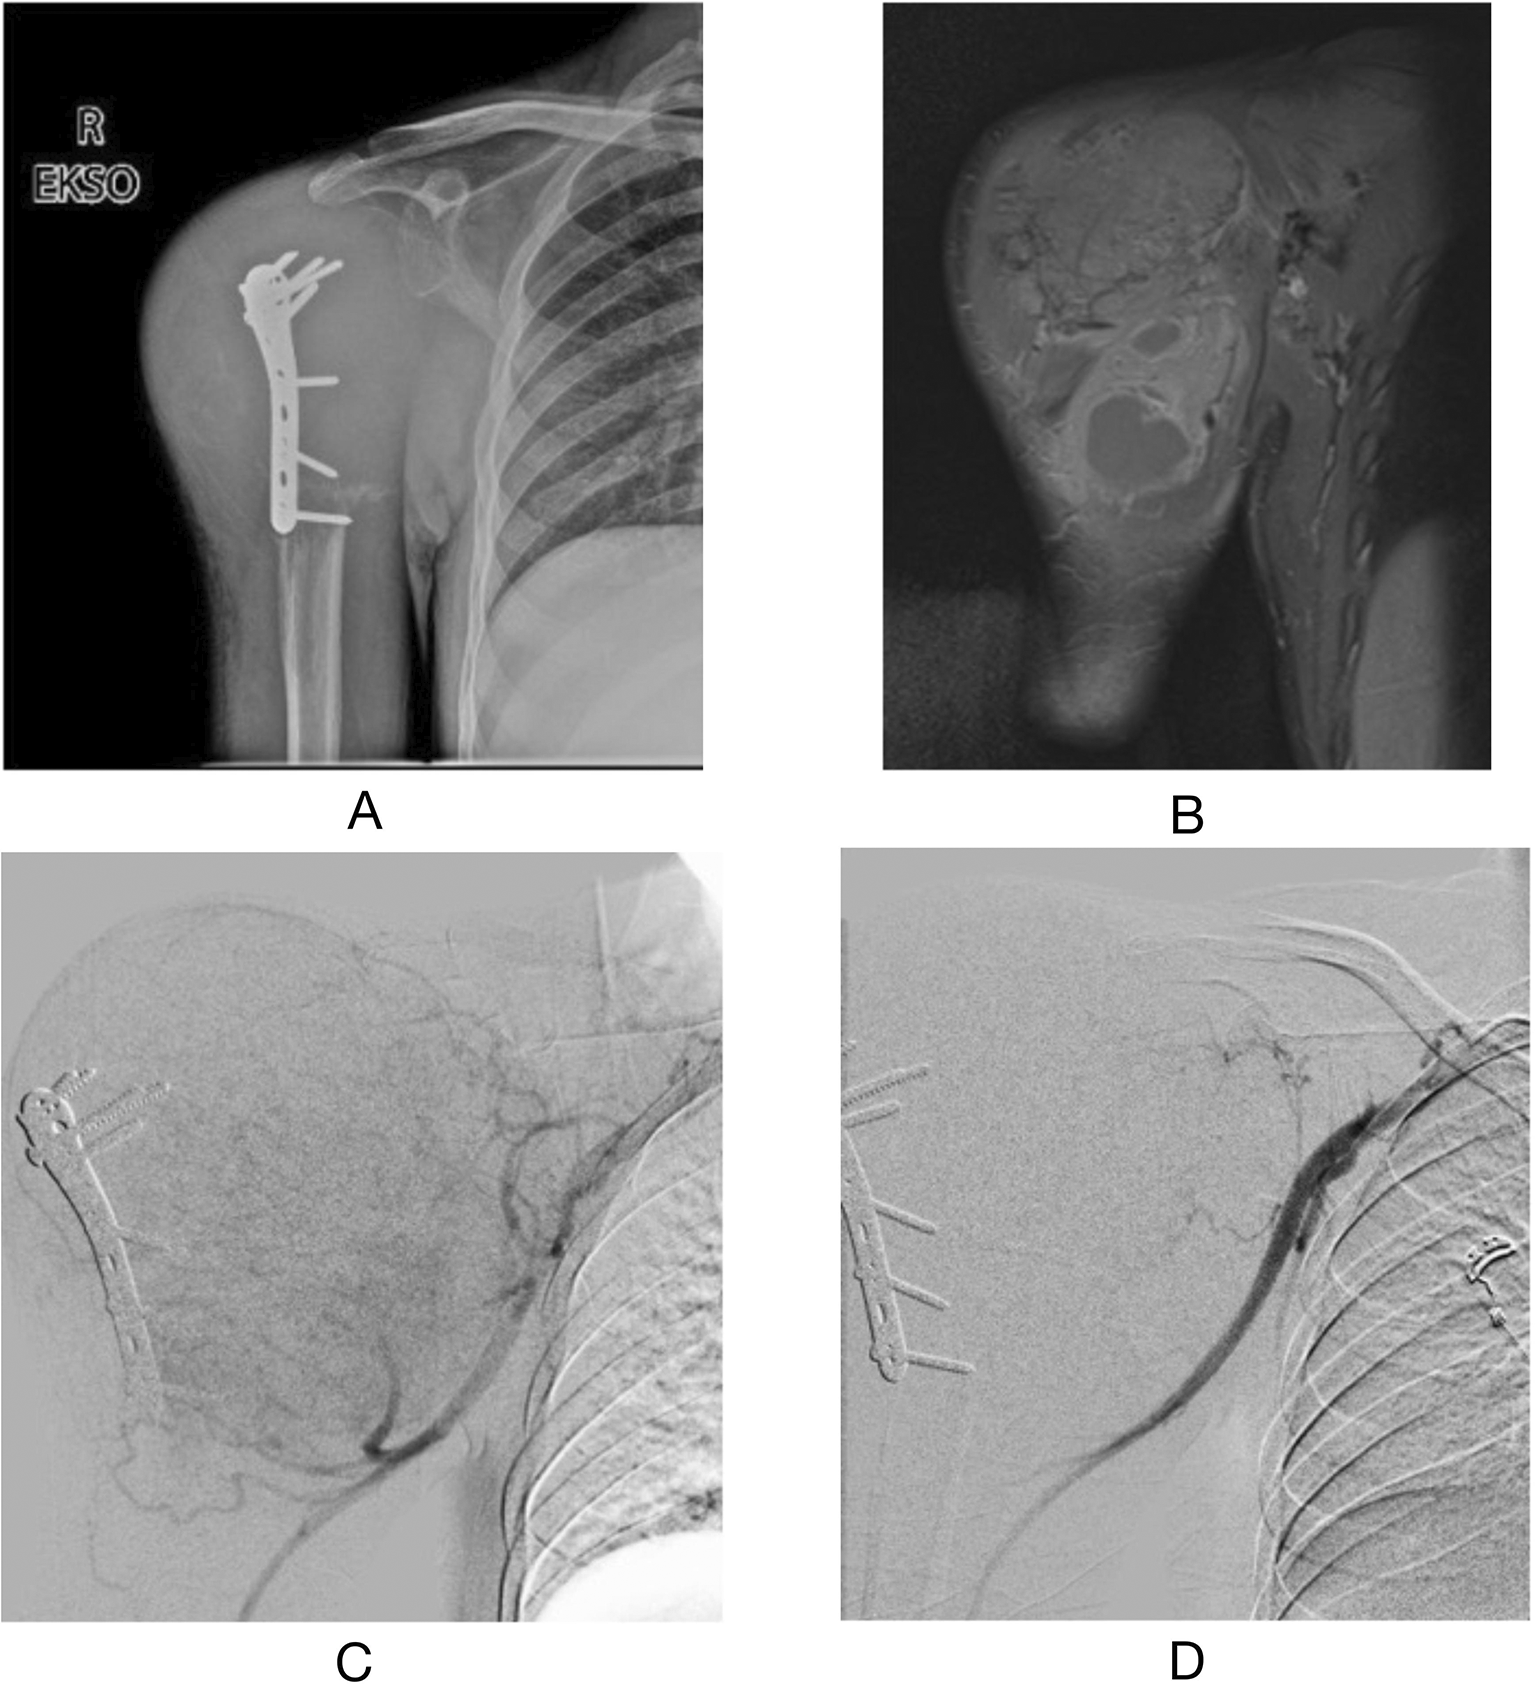

A 22-year-old man was referred to the Interventional Radiology department for preoperative endovascular embolization a day prior to resection of a giant cell tumor with an aneurysmal bone cyst in the proximal right humerus. The tumor was initially as small as a tennis ball but eventually grew larger until it became as large as the whole upper shoulder. Based on physical examination, a 17 × 16 × 9 cm mass was measured on the upper right humerus. Preoperative magnetic resonance imaging (MRI) with gadolinium contrast revealed heterogeneous lytic lesions in the epimetaphysis until the mid-diaphysis right humerus, lobulated, septate with malignant characteristic expanded, and pushing the muscle component around the lesion in all directions. Because the surgery was thought to have massive bleeding, preoperative embolization was performed. During the procedure, hypervascularity was found to be supplied by the branches of the axillary, brachial, and deep brachial arteries. Embolization was performed with a Vertebral 5F catheter, super selectively with Progreat 2.7 microcatheter, and Gelfoam®, following which the hypervascularity was no longer found. Tumor resection following the procedure was successfully performed, with 1,500 mL of blood loss. The patient was discharged seven days after surgery. Six months after the surgery, the patient had already visited for a follow-up examination, with no recurrence noted (Figure 1).

(A) preoperative right shoulder X-ray AP position (B) preoperative T1-weighted MRI with Gadolinium contrast administration (C) angiography following procedure (D) angiography post embolization procedure.